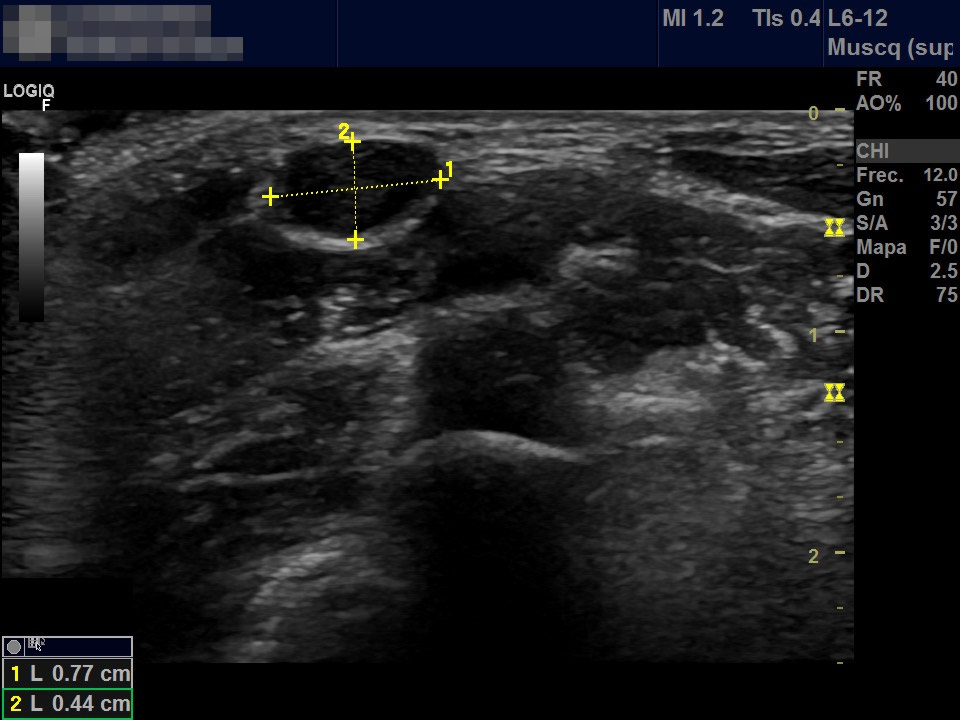

Niño de 7 años que acude a consulta de Atención Primaria por aparición de tumoración cervical de 2 días de evolución. A la exploración en la región lateral cervical posterior al esternocleidomastoideo se aprecia una tumoración móvil no adherida de consistencia blanda de aproximadamente 1 cm de diámetro sin cambios superficiales acompañantes. No presenta otra clínica sistémica asociada. Antecedentes personales y familiares sin interés. No habían observado similar lesión en otras ocasiones. Realizamos ecografía simple (Figura 1) y ecografía Doppler de la lesión (Figura 2).

Figura 1. Estructura ovalada de bordes netos con contenido hipoecogénico de 0,7 x 0,4 mm, con zona central levemente hiperecogénica.